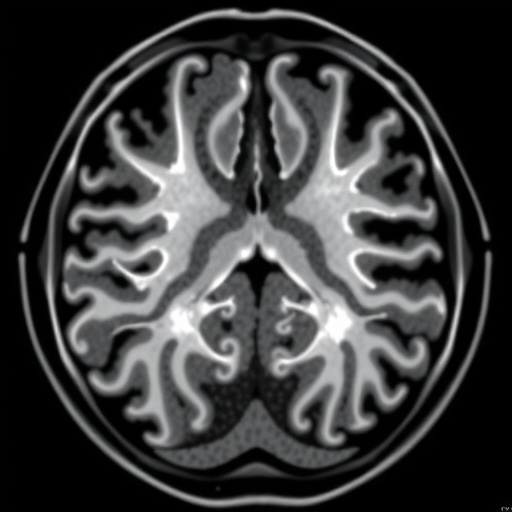

The study cohort comprised adults who, as neonates, received open esophageal atresia repair. Over the past years, these individuals have faced variable respiratory challenges, yet conventional static imaging and pulmonary function tests have failed to elucidate the nuanced interplay between lung capacity fluctuations and muscular skeletal constraints. Real-time MRI techniques overcame these limitations by capturing live respiratory motion, allowing assessment not only of static anatomical abnormalities but also of dynamic airway behavior and chest wall kinetics throughout the breathing cycle.

Importantly, the imaging sequences used were tailored to visualize high-temporal-resolution thoracic anatomy without ionizing radiation, thus providing a safe method suitable for longitudinal follow-up studies. The researchers meticulously quantified parameters such as diaphragm excursion, rib cage expansion, and ventilatory patterns during different respiratory phases. This approach shed light on the compensatory mechanisms elicited by residual structural irregularities and provided compelling evidence that esophageal atresia repair has lasting ramifications extending beyond the initial anatomical correction.

One of the more surprising outcomes of the investigation was the revelation that even in the absence of overt clinical symptoms, subtle functional impairments could be detected by real-time MRI—highlighting its sensitivity and potential as a prognostic tool. These subclinical presentations could have been easily overlooked with standard diagnostic methods, underscoring the importance of advanced imaging in the comprehensive evaluation of this unique patient population.